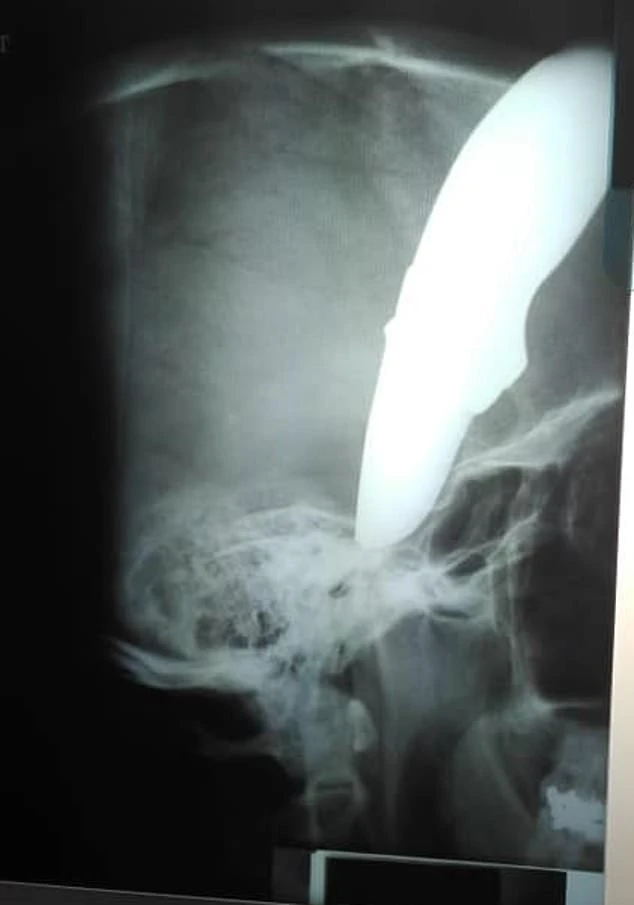

Phim chụp X-quang cho thấy con dao đâm sâu vào đầu nạn nhân. Ảnh: Daily Mail

"Anh ấy lịch sự yêu cầu được gặp bác sĩ, đồng thời tỏ ra bình tĩnh và tỉnh táo mặc dù chảy máu rất nhiều. Tuy nhiên, Wayne đã rất may mắn vì con dao đâm vào hộp sọ nhưng bị cong do chạm trúng xương. Lưỡi dao chệch xuống mặt bệnh nhân bên ngoài hộp sọ" – BS Brendan Venter, 48 tuổi, nói với Daily Mail.